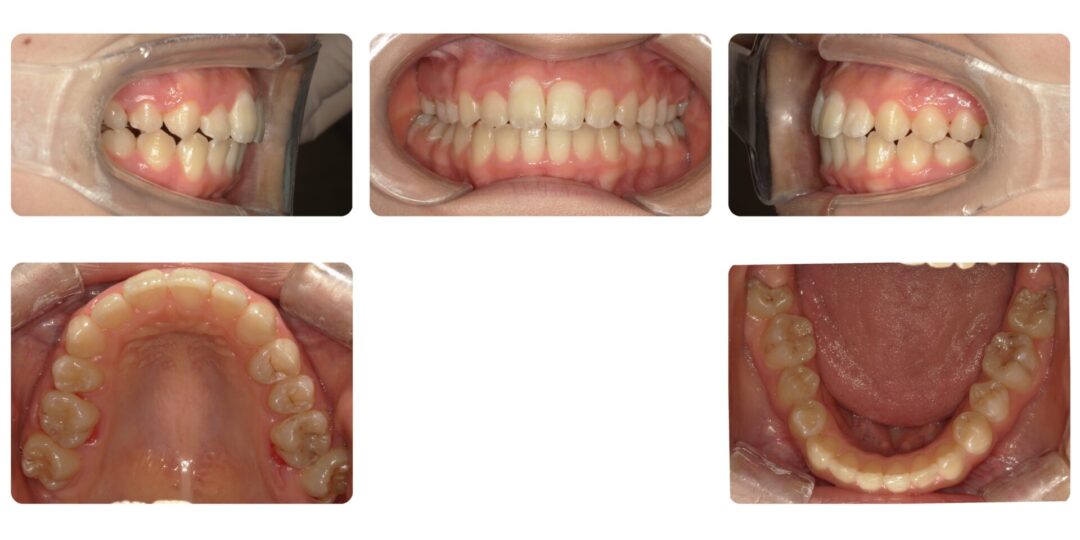

矯正治療後